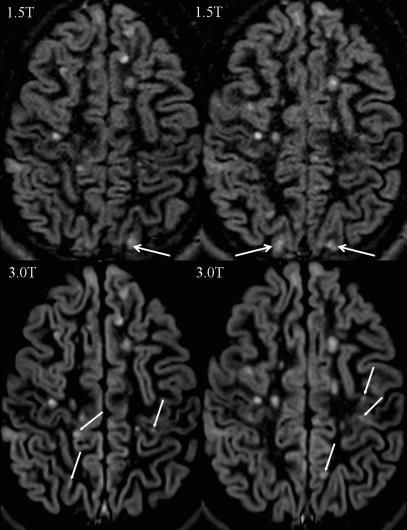

To investigate the impact of a higher magnetic field strength of 3 Tesla (T) on the detection rate of cortical lesions in multiple sclerosis (MS) patients, in particular using a dedicated double inversion recovery (DIR) pulse sequence.

Thirty-four patients with clinically isolated syndromes or definite MS were included. All patients underwent magnetic resonance imaging (MRI) at 1.5 T and 3 T, including T2-weighted turbo spin echo (TSE), fluid-attenuated inversion recovery (FLAIR) and DIR sequences. All images were analysed for focal lesions categorised according to their anatomical location.

The total number of detected lesions was higher at 3 T across all pulse sequences. We observed significantly higher numbers of lesions involving the cortex at 3 T using a DIR sequence. DIR at 3 T showed 192% more pure intracortical (p < 0.001) and 30% more mixed grey matter-white matter lesions (p = 0.008). No significant increase in cortical lesions could be detected on the FLAIR and T2-weighted images. Using the T2-weighted and FLAIR sequences, significantly more lesions could be detected at 3 T in the infratentorial, periventricular and juxtacortical white matter.

DIR brain MR imaging at 3 T substantially improves the sensitivity of the detection of cortical lesions compared with the standard magnetic field strength of 1.5 T.

研究磁场强度为 3 特斯拉(T)对多发性硬化症(MS)患者皮质病变检出率的影响,特别是使用专用双反转恢复(DIR)脉冲序列。

纳入 34 例临床孤立综合征或明确 MS 患者。所有患者均在 1.5T 和 3T 行磁共振成像(MRI)检查,包括 T2 加权快速自旋回波(TSE)、液体衰减反转恢复(FLAIR)和 DIR 序列。所有图像均根据解剖位置进行局灶性病变分类分析。

在所有脉冲序列中,3T 检测到的病变总数均较高。使用 DIR 序列时,我们观察到 3T 时皮质病变数量显著增加。3T 下的 DIR 序列显示,单纯皮质内病变增加了 192%(p<0.001),灰质-白质混合病变增加了 30%(p=0.008)。FLAIR 和 T2 加权图像上未检测到皮质病变的显著增加。在使用 T2 加权和 FLAIR 序列时,3T 下后颅窝、脑室周围和皮质下白质的病变数量显著增加。

与标准磁场强度 1.5T 相比,3T 的 DIR 脑 MRI 可显著提高皮质病变的检出敏感性。